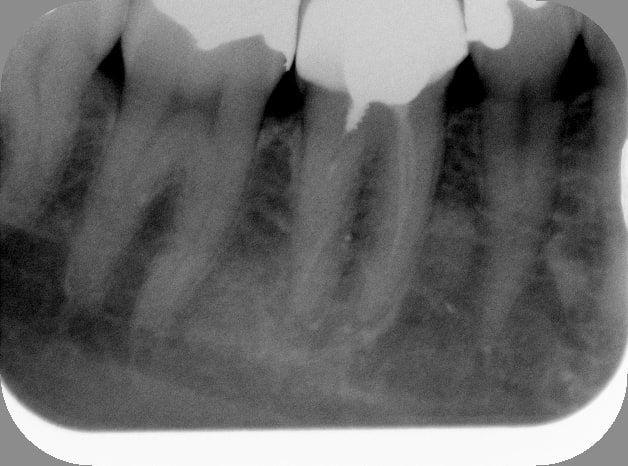

Bon allez, je le kiffe.

Et la pâte dans le dentaire inf c'est pas de moi.